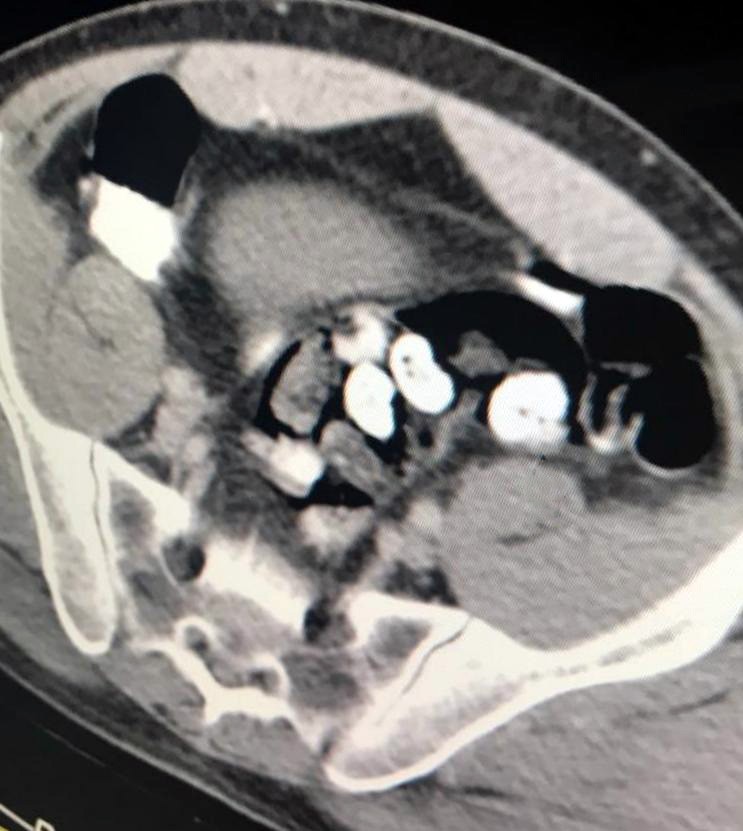

Burada zanlının bağırsak tomografisi çekildi. Bağırsaklarında serçe parmağı büyüklüğünde yabancı cisimler olduğu tespit edilmesine rağmen zanlı, uyuşturucu olmadığını ileri sürmeye devam etti.

Doktorlar zanlıya özel bir ilaç vererek bağırsaklarında yabancı cisimlerin tuvalet yoluyla çıkmasını sağladı. 5 günün sonunda zanlının bağırsaklarından 4 pakette 116 gram metamfetamin, 21 pakette 104 gram eroin, 22 pakette 107 gram afyon sakızı çıktı.